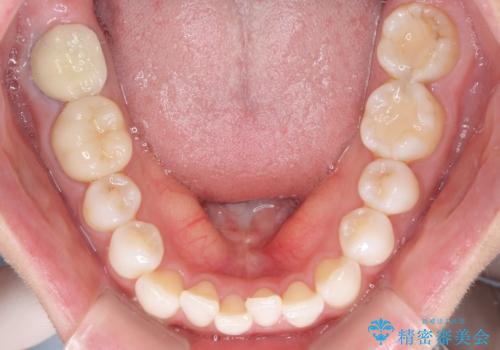

軽度の叢生をインビザライン・ライトで解消

- 前歯が気になるとのことで来院された患者様です。

歯列不正は軽微であったため、インビザライン・ライトにより、費用を抑えて矯正治療を行うこととしました。

短期間で気になる前歯の歯列を改善することができました。